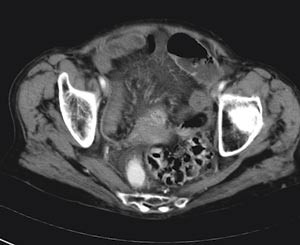

Tre timer etter innleggelsen og 19 timer etter symptomdebut ble pasienten laparotomert. Man fant hemoragiske forandringer på tynntarmsserosa i en lengde på 50 cm av distale ileum ned mot ileocøkalovergangen. Oralt for disse forandringene var det en adheransestreng som forsårsaket strangulasjonen. Etter at strengen ble delt og tynntarmsmesenteriet brettet ut, fikk man god oversikt over de makroskopiske forandringene (fig 4). Det var ingen tegn til tarmnekrose. Man observerte det affiserte tynntarmssegmentet i 15 minutter. Tarmsegmentet virket da vitalt og velsirkulert, og tarmreseksjon ble ikke funnet nødvendig. Undersøkelse i abdomen for øvrig avdekket ingen annen patologi, bortsett fra små divertikler i sigmoideum. Det postoperative forløpet var ukomplisert. Pasienten ble utskrevet til sitt eget hjem 10. postoperative dag i god allmenntilstand.